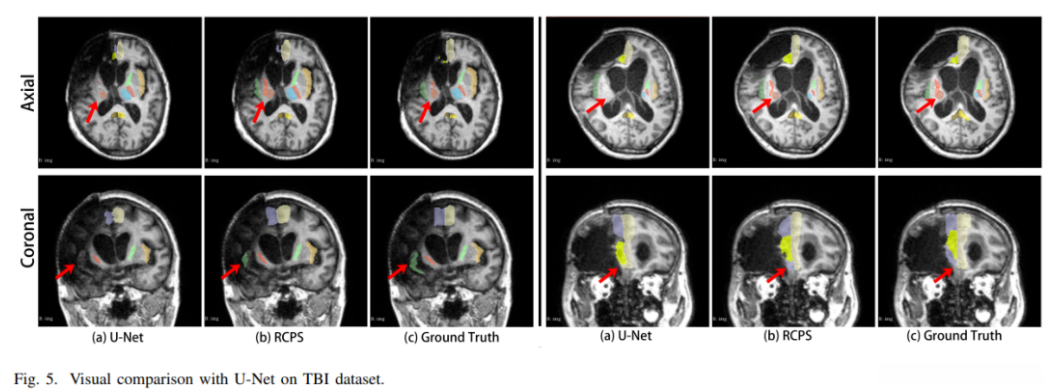

Visual comparison with other methods on TBI dataset

基于TBI数据集上,在采用我们提出的半监督学习方法进行训练后,该模型不仅能够识别并划分全监督学习中通常被忽视的结构单元,并且输出的结果相较于传统全监督方法具有更为精细的空间划分能力。 chaosisoft aiot http://143ai.com